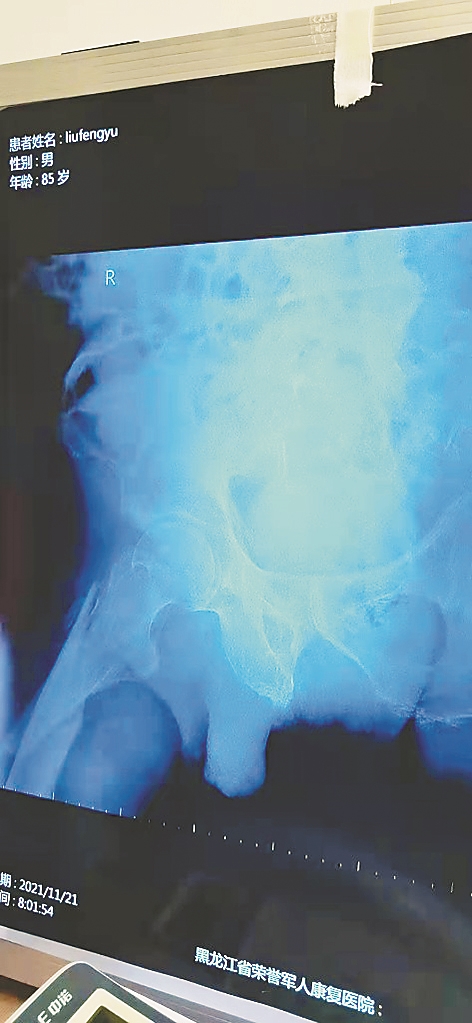

马先生表示,事发后护养院工作人员给老人家属发的X光片显示,老人股骨骨折。事发后,老人家属多次向有关部门反映,护养院工作人员给家属了一份情况说明——关于“意外骨折事件家属索要处理意见的答复”中写道:“11月21日7时许,早饭前在工作人员查房过程中发现老人右腿疑似背折症状,8点15分转入医院相关科室进行相关检查,影像结果经医生与哈尔滨市第五医院骨科专家查阅后所得结果为,老人右侧股骨闭合性骨折并伴有重度骨质疏松(骨小梁消失),同时院方针对老人骨折的原因,对其护理人员与同室居住其他老人或有可能了解详情的所有人员进行了相关调查,当日房间内并无异常,老人没有下过床,也未与任何人产生过任何争执,老人右腿无任何外伤,综合骨科专家对其斜性骨折接口分析,调查所得结果指向疑似骨折原因为:20日18时许在护理人员为老人更换衣物时造成此次骨折意外。”马先生表示,这份情况说明并没有落款单位和公章。